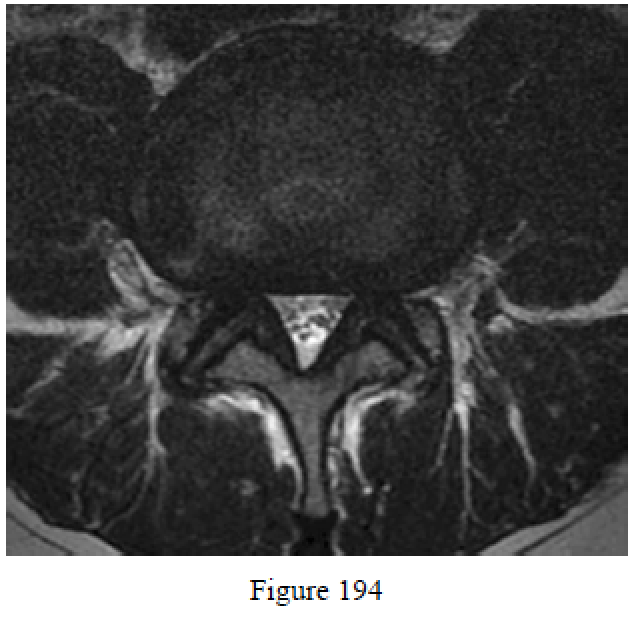

Question 194

Figure 194 is the MR image of a 73-year-old man with hypertension who has a 10-week history of bilateral leg pain when he walks more than 2 blocks. A complete evaluation should include a(n)